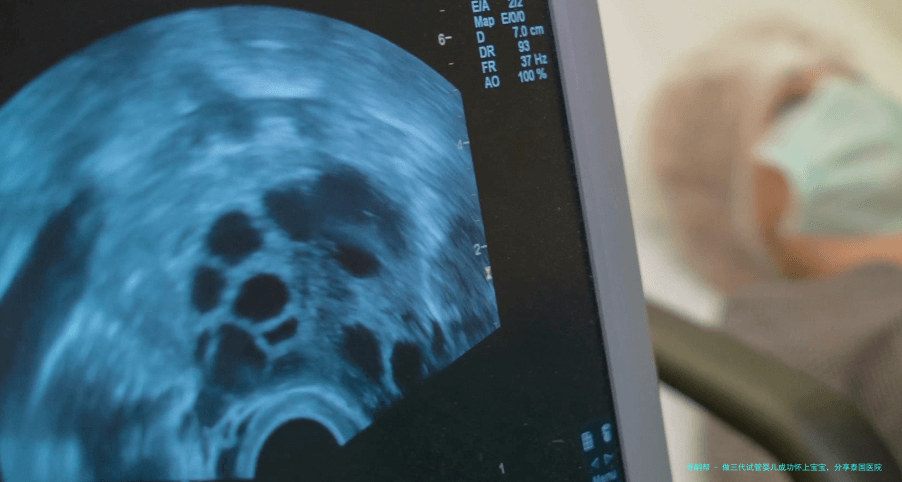

结果出来后见医生,医生给做阴道B超,护士给了一个小裙子更换上,很人类本性化,如此避免了很多小尴尬。

医生问的很仔细,全程看着我,很重视我讲述的每一个细节,反复问清晰。医生说我的子宫情况非常好,基础卵泡有5个,加上还要选� ,年龄大,就看能不能得到正常的胚胎。